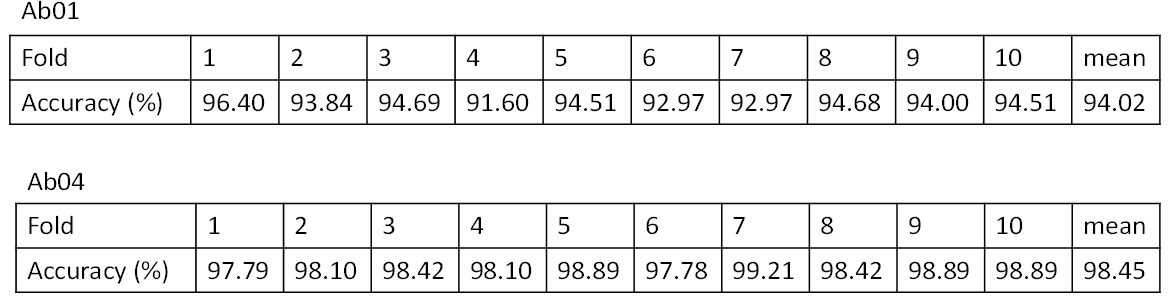

Sample data set에 대한 학습결과는 다음과 같음

데이터 성능 점수

측정값 (%)기준값 (%)데이터 성능 지표

데이터 성능 지표 번호 측정항목 AI TASK 학습모델 지표명 기준값 점수 측정값 점수 1 반려동물 질환 진단 정확도(사지골절(Mu02)) Object Detection Faster-RCNN F1-Score@IoU 0.5 0.7 점 0.7631 점 2 반려동물 질환 진단 정확도(엉덩관절탈구(Mu04)) Object Detection Faster-RCNN F1-Score@IoU 0.5 0.7 점 0.7096 점